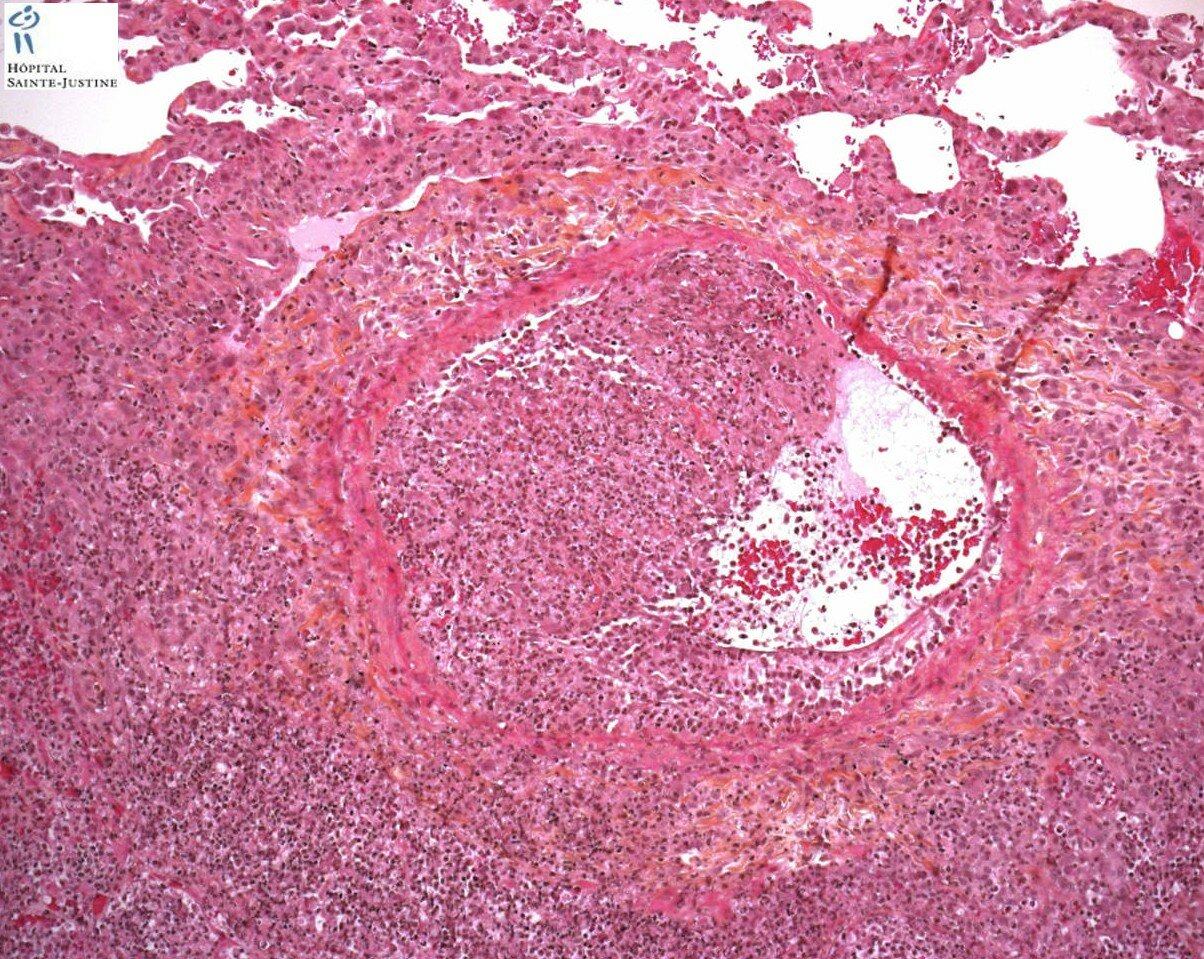

invasive pulmonary aspergillosis

Invasive pulmonary aspergillosis Invasive pulmonary aspergillosis Invasive pulmonary aspergillosis invasive pulmonary aspergillosis invasive pulmonary aspergillosis invasive pulmonary aspergillosis invasive pulmonary aspergillosis invasive pulmonary aspergillosis invasive pulmonary aspergillosis invasive pulmonary aspergillosis invasive pulmonary aspergillosis invasive pulmonary aspergillosis invasive pulmonary aspergillosis invasive pulmonary aspergillosis Invasive pulmonary aspergillosis